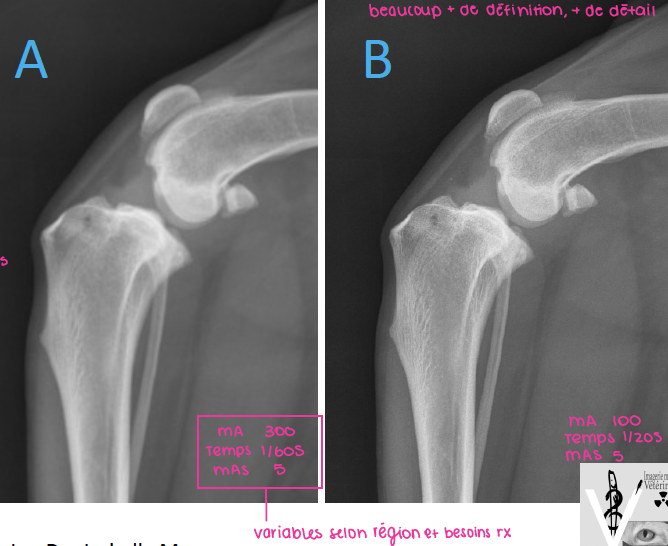

Q

Laquelle des deux radiographies a été prise avec un filament de taille plus petite?

A

la B)

en effet, un filament plus petit offrira une radiographie avec plus de détails